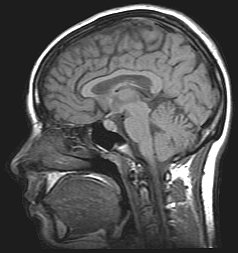

Magnetic Resonance Imaging creates images from the magnetic behaviour of hydrogen protons in brain tissue, and so can show more detail (down to around 1mm) than Computed Tomography. These imaging methods are mainly used to investigate anatomical structures and the processes associated with disease, not the dynamic functioning of the brain.

Functional Magnetic Resonance Imaging (fMRI), on the other hand, is a brain research method which scientists use to deduce how the brain operates. Because oxygenated haemoglobin and deoxygenated haemoglobin have different magnetic properties, they look very different in this type of scan. Using this method, scientists can therefore see when and where there is increased blood flow to different parts of the brain. Most scientists believe this increased blood flow is a sign of increased brain activity. The debate about what this means is just one of the interesting aspects of fMRI.